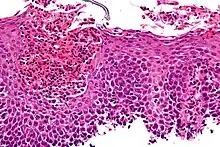

The esophagus is a muscular tube made of both voluntary and involuntary muscles. It is responsible for peristalsis of food. It is about 8 inches long and passes through the diaphragm before entering the stomach. The esophagus is made up of three layers: from the inside out, they are the mucosa, submucosa, muscularis externa. The mucosa, the inner most layer and lining of the esophagus, is composed of stratified squamous epithelium, lamina propria, and muscularis mucosae. At the end of the esophagus is the lower esophageal sphincter, which normally prevents stomach acid from entering the esophagus.

If the sphincter is not sufficiently tight, it may allow acid to enter the esophagus, causing inflammation of one or more layers. Esophagitis may also occur if an infection is present, which may be due to bacteria, viruses, or fungi; or by diseases that affect the immune system.[4]

Laboratory tests can be done on biopsies removed from the esophagus and can help determine the cause of the esophagitis. Laboratory tests can help diagnose a fungal, viral, or bacterial infection. Scanning for white blood cells can help diagnose eosinophil esophagitis.

Eosinophilic esophagitis is caused by a high concentration of eosinophils in the esophagus. The presence of eosinophils in the esophagus may be due to an allergen and is often correlated with GERD. The direction of cause and effect between inflammation and acid reflux is poorly established, with recent studies (in 2016) hinting that reflux does not cause inflammation.[6] This esophagitis can be triggered by allergies to food or to inhaled allergens. This type is still poorly understood.

Lymphocytic esophagitis is a rare and poorly understood entity associated with an increased amount of lymphocytes in the lining of the esophagus.[1] It was first described in 2006. Disease associations may include Crohn's disease, gastroesophageal reflux disease and coeliac disease. It causes similar changes on endoscopy as eosinophilic esophagitis including esophageal rings, narrow-lumen esophagus, and linear furrows.